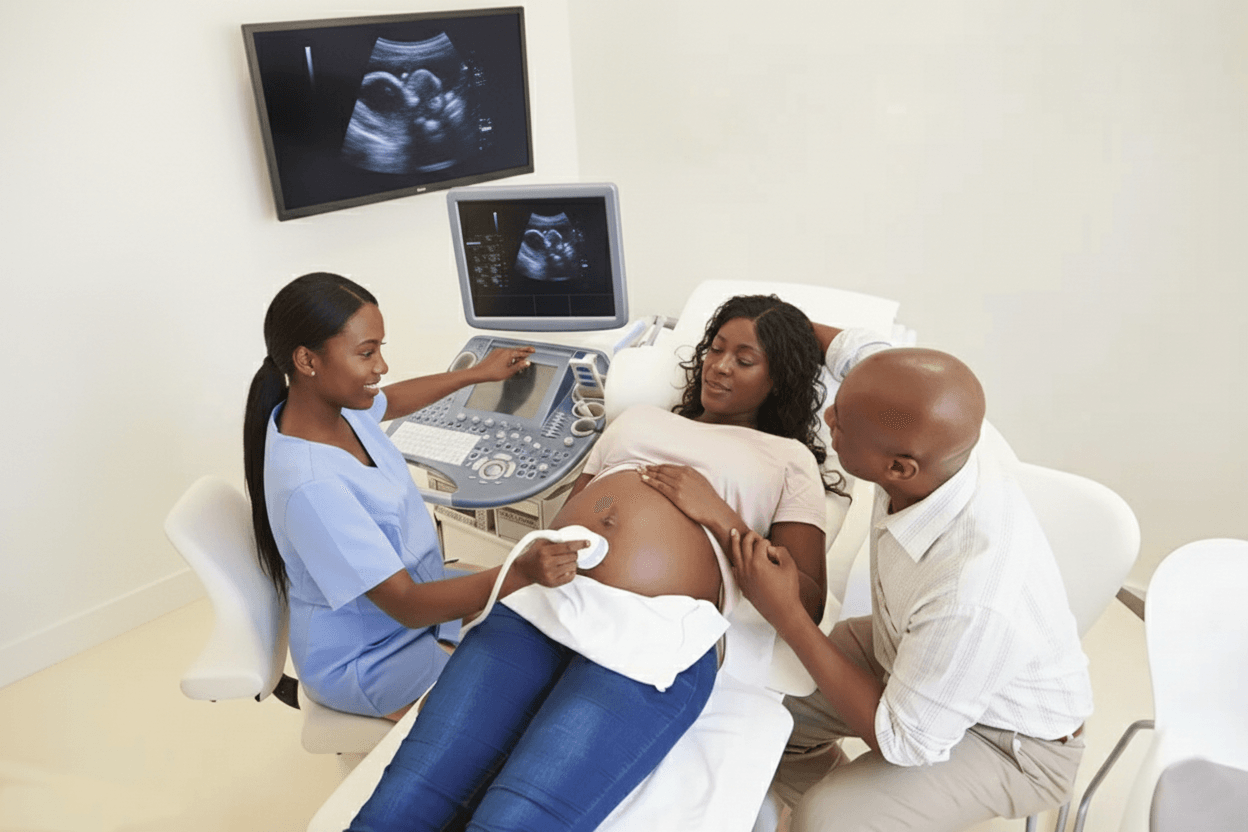

State-of-the-art ultrasound imaging including pelvic, abdominal, obstetric, thyroid, and Doppler scans.

"The ultrasound scan gave us peace of mind during my pregnancy. The staff were incredibly professional, caring, and took time to explain everything. I felt safe and well cared for throughout the entire process. Highly recommend Integris Health to all expecting mothers!"

Abena Osei

Expectant Mother